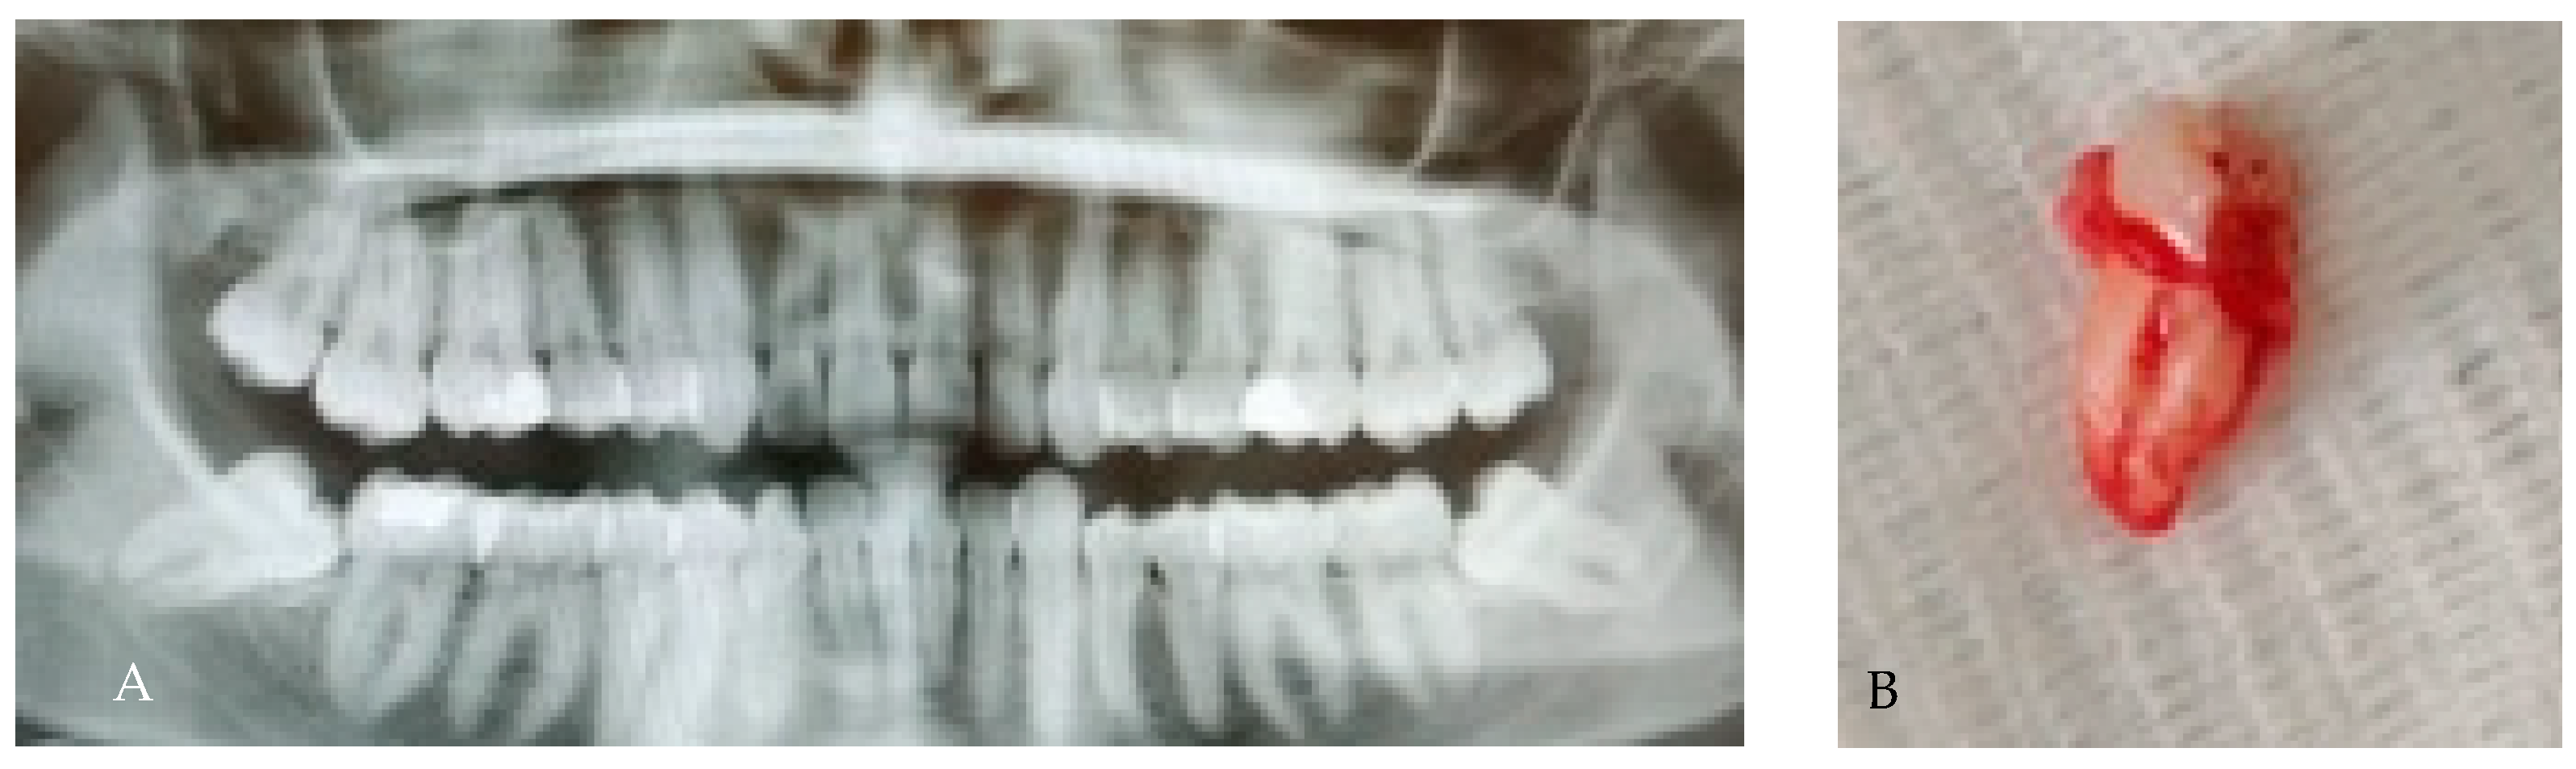

3.1. Root Number Variation (Single, Two, Three or More Roots)

3.2. Radix Entomolaris

3.3. Radix Paramolaris